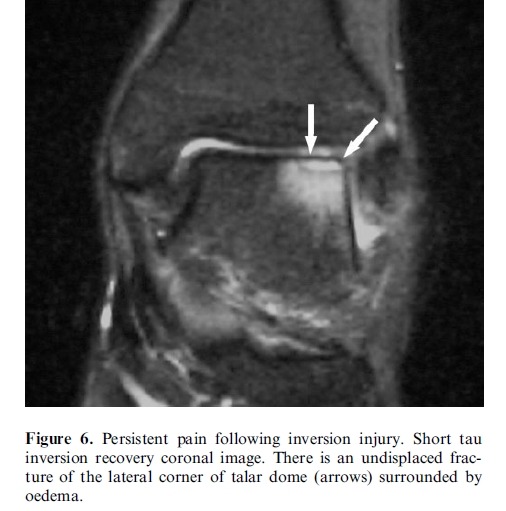

Subtle osteochondral fracture of the lateral corner of the talar dome